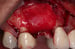

Following a GBR at the time of implant placement (Pictures 1,2,3), a buccal ridge deficiency persisted (Picture 4). Surgical uncovery of the implant to expose the cover screw revealed successful bone regeneration around the implant, but a residual lack of ridge contour (Picture 5).

Instead of using a traditional particulate graft covered with a resorbable membrane, a “flexible bone graft” sheet, DALI Flex Graft, was placed over the buccal plate to augment the buccal contour (Pictures 6 & 7). Because the graft comes hydrated, it is easy to handle and adapt to the defect location. The flap was then pulled over the graft and adapted around the healing abutment (Picture 8).